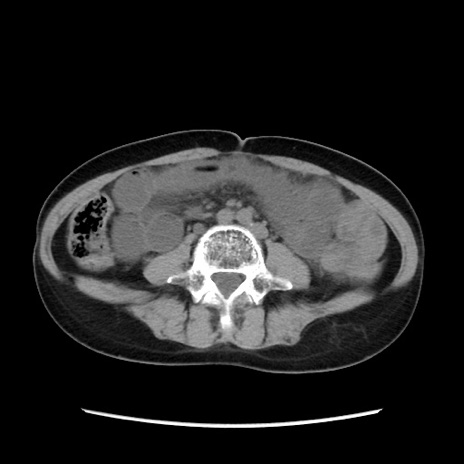

症例32(横断像)

【症例】40歳代 女性

【主訴】上腹部痛、嘔気・嘔吐

【現病歴】約9時間前頃から急に上腹部痛、嘔気、嘔吐が出現。改善しないため救急要請。

【既往歴】子宮頚癌(広汎子宮全摘術、放射線療法)、腸閉塞

【身体所見】腹部:平坦、軟、腸雑音亢進、上腹部を中心に腹部全体に圧痛あり。

【データ】WBC 8400、CRP 0.03